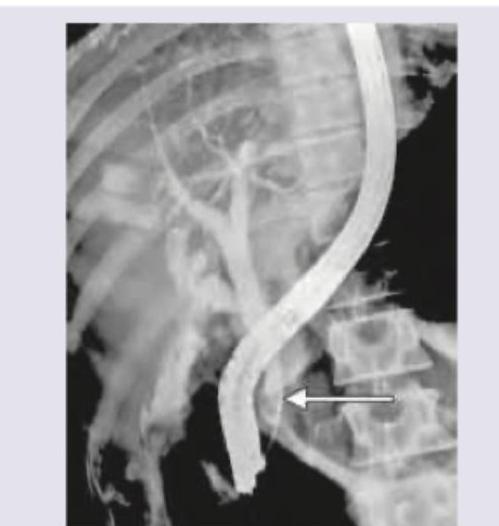

The following image shows:

Explanation: ***ERCP showing smooth filling defect*** - The image displays a **retrograde filling** of the biliary tree with contrast, characteristic of an **Endoscopic Retrograde Cholangiopancreatography (ERCP)**. - The arrow points to a smooth, crescent-shaped defect within the common bile duct, consistent with a **gallstone (choledocholithiasis)** causing a filling defect. *PTC showing smooth filling defect* - **Percutaneous Transhepatic Cholangiography (PTC)** involves an antegrade injection of contrast directly into the intrahepatic bile ducts through the skin, which is not what is seen here. - While PTC can show filling defects, the **retrograde cannulation** of the common bile duct from the duodenum is clearly visible, ruling out PTC. *Oral cholecystogram showing stricture* - An **oral cholecystogram** assesses gallbladder function and stones, not the common bile duct as clearly visualized here. - There is no evidence of a **stricture**, which would appear as a focal narrowing with upstream dilation, instead, a filling defect is central to the finding. *HIDA scan showing cystic duct agenesis* - A **HIDA scan (Hepatobiliary Iminodiacetic Acid scan)** is a nuclear medicine study that assesses gallbladder function and bile flow, not anatomical details of the biliary tree in the same way as a contrast study. - **Cystic duct agenesis** would manifest as the absence of gallbladder visualization, which cannot be determined from this image.